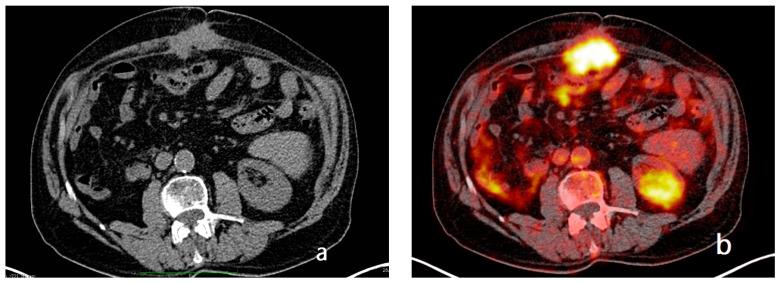

Peritoneal carcinosis is a condition characterized by the spread of cancer cells to the peritoneum, which is the thin membrane that lines the abdominal cavity. It is a serious condition that can result from many different types of cancer, including ovarian, colon, stomach, pancreatic, and appendix cancer. The diagnosis and quantification of lesions in peritoneal carcinosis are critical in the management of patients with the condition, and imaging plays a central role in this process. Radiologists play a vital role in the multidisciplinary management of patients with peritoneal carcinosis. They need to have a thorough understanding of the pathophysiology of the condition, the underlying neoplasms, and the typical imaging findings. In addition, they need to be aware of the differential diagnoses and the advantages and disadvantages of the various imaging methods available. Imaging plays a central role in the diagnosis and quantification of lesions, and radiologists play a critical role in this process. Ultrasound, computed tomography, magnetic resonance, and PET/CT scans are used to diagnose peritoneal carcinosis. Each imaging procedure has advantages and disadvantages, and particular imaging techniques are recommended based on patient conditions. Our aim is to provide knowledge to radiologists regarding appropriate techniques, imaging findings, differential diagnoses, and treatment options. With the advent of AI in oncology, the future of precision medicine appears promising, and the interconnection between structured reporting and AI is likely to improve diagnostic accuracy and treatment outcomes for patients with peritoneal carcinosis.

腹膜癌是一种以癌细胞扩散至腹膜为特征的病症,腹膜是衬于腹腔的一层薄膜。它是一种严重的病症,可由多种不同类型的癌症引发,包括卵巢癌、结肠癌、胃癌、胰腺癌和阑尾癌。腹膜癌中病变的诊断和定量对于该病症患者的管理至关重要,而影像学在这一过程中发挥着核心作用。放射科医生在腹膜癌患者的多学科管理中起着至关重要的作用。他们需要对该病症的病理生理学、潜在肿瘤以及典型的影像学表现有透彻的了解。此外,他们需要知晓鉴别诊断以及各种可用影像学方法的优缺点。影像学在病变的诊断和定量中起着核心作用,放射科医生在这一过程中起着关键作用。超声、计算机断层扫描、磁共振成像和正电子发射断层显像/计算机断层扫描(PET/CT)用于诊断腹膜癌。每种成像检查都有其优缺点,会根据患者情况推荐特定的成像技术。我们的目的是向放射科医生提供有关合适技术、影像学表现、鉴别诊断和治疗方案的知识。随着人工智能在肿瘤学中的出现,精准医学的未来似乎很有前景,结构化报告与人工智能之间的相互联系可能会提高腹膜癌患者的诊断准确性和治疗效果。